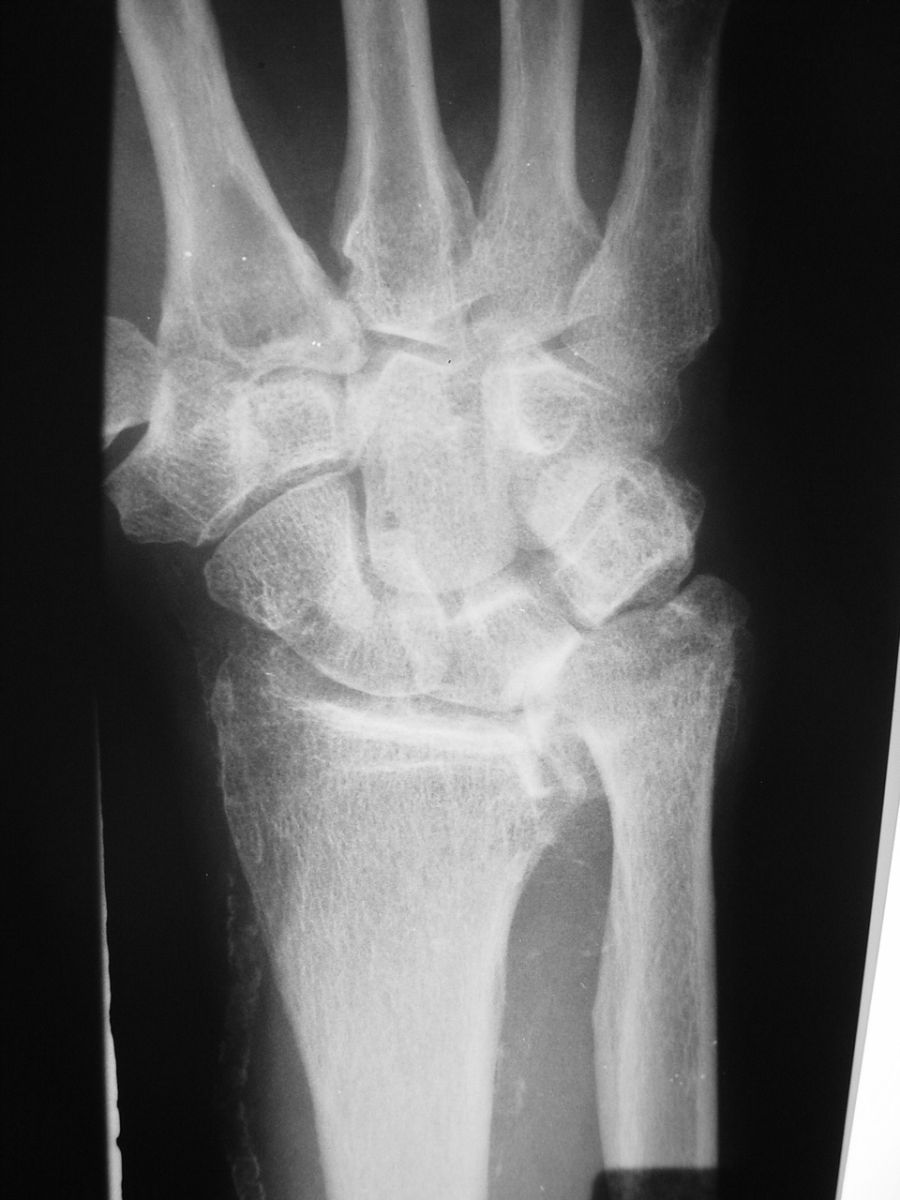

| Case 1. This 80 year old man developed wrist and elbow pain years after radial head excision for fracture. Radiographs show proximal migration of the radius resulting in valgus instability of the elbow, radiocapitellar impingement and distal ulnar impaction. This pattern of longitudinal forearm disruption, proximal radial fracture and dislocation of the distal radioulnar joint, is referred to as the Essex-Lopresti fracture dislocation. |